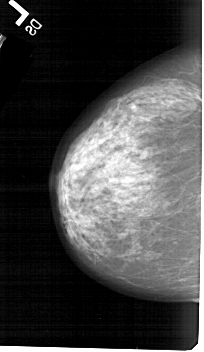

A_1322_1.RIGHT_CC

LEFT_CC LINES 5266 PIXELS_PER_LINE 3046 BITS_PER_PIXEL 12 RESOLUTION 43.5 NON_OVERLAY